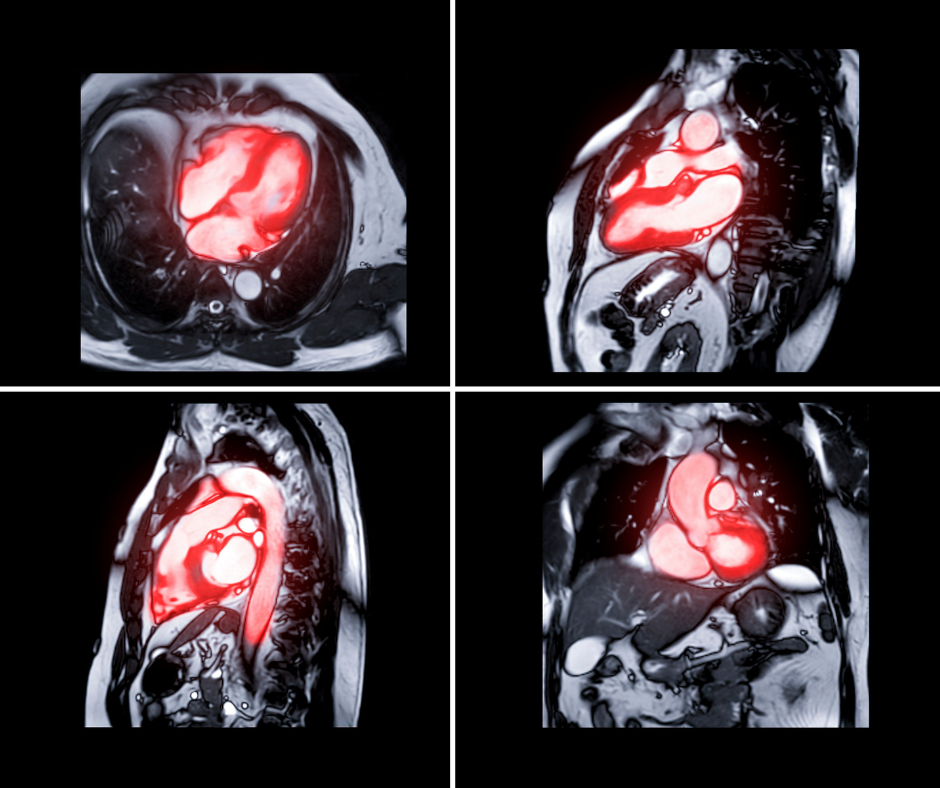

In a review of the literature, this author discusses the viability of artificial intelligence (AI), parallel imaging, compressed sensing and simultaneous multi-slice excitation for improving the scan times and use of magnetic resonance imaging (MRI) to facilitate CyberKnife treatment.